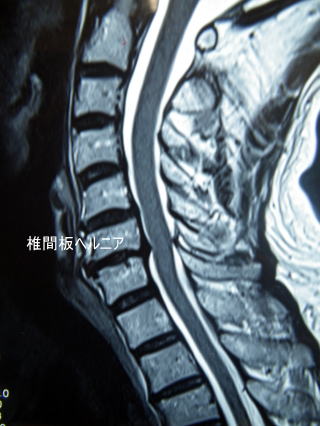

頚椎椎間板ヘルニア cervical disc herniation

C6/7で椎間板ヘルニアを認める。

いずれにせよ神経症状がある人はレントゲンに加えてMRIによる検索を行い、症状と合致する異常所見があるか調べます。統計的には1%の確率(100人に1人)で癌や癌の転移が生じていることがあります。